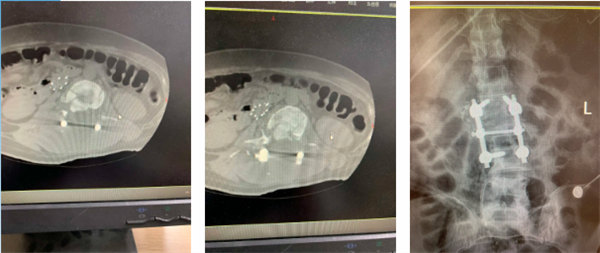

術后影像

入院后三天,手術團隊分“兩路”在全麻狀態下為患者實施了手術治療。首先由胸外科主任陳瑜團隊為患者行“左側部分肋骨骨折切口復位內固定術+左側胸腔鏡探查術”,隨后在胸外科團隊保駕護航下,骨一科副主任王文亮團隊為患者行“腰Ⅱ椎體爆裂性骨折切開復位內固定術+椎板切開減壓術”。在麻醉手術科、重癥醫學科、輸血科等多學科的協作配合下,手術順利完成。術后第二天,患者左下肢肌力恢復至III級,右下肢肌力I級。